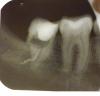

Redgi Опубликовано 7 декабря, 2012 Поделиться Опубликовано 7 декабря, 2012 Здравствуйте! После депульпирования постоянная пульсирующая боль не проходит уже 3 недели. Антибиотики не помогли. Стоматолог говорит, что на снимке все хорошо, но снимок мне не дала. Через 2 недели распломбировали, поставили временную пломбу и лекарство. Сказали, что если боль не пройдет, нужно удалить зуб. Пошла к другому стоматологу, сделали снимок, на снимке обнаружили кисту и посоветовали полоскания содой с йодом. Скажите, пожалуйста, почему образовалась киста и можно ли ее вылечить. Удалять зуб не хочется. Да еще сказали, что каналы очень узкие и кривые. На снимке видно, что что-то "уходит" в десну (7 зуб). Объясните, пожалуйста, это канал или пломбировочный материал? Так должно быть? Ссылка на комментарий

shishok Опубликовано 7 декабря, 2012 Поделиться Опубликовано 7 декабря, 2012 Кисты там нет,но зуб всё таки удалять. Ссылка на комментарий

IvanK Опубликовано 8 декабря, 2012 Поделиться Опубликовано 8 декабря, 2012 Кисты там нет,но зуб всё таки удалять.+1 Ссылка на комментарий